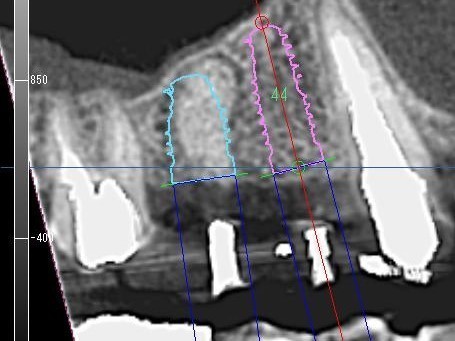

③埋入方向確認

歯科用CTとインプラントシミュレーションソフトによる事前の治療計画

また、事前検査にも負担軽減の工夫をしています。インプラントを埋め込むあごの骨には、重要な神経や血管があり、そこを誤って傷つけるようなことがあってはなりません。そのような危険性をできる限り少なくするためには、術前の精密な検査や診断が重要となります。そこでCTによる検査を行うことで、手術中の事故を防ぎ、より安全に治療を行えるよう努めているのです。